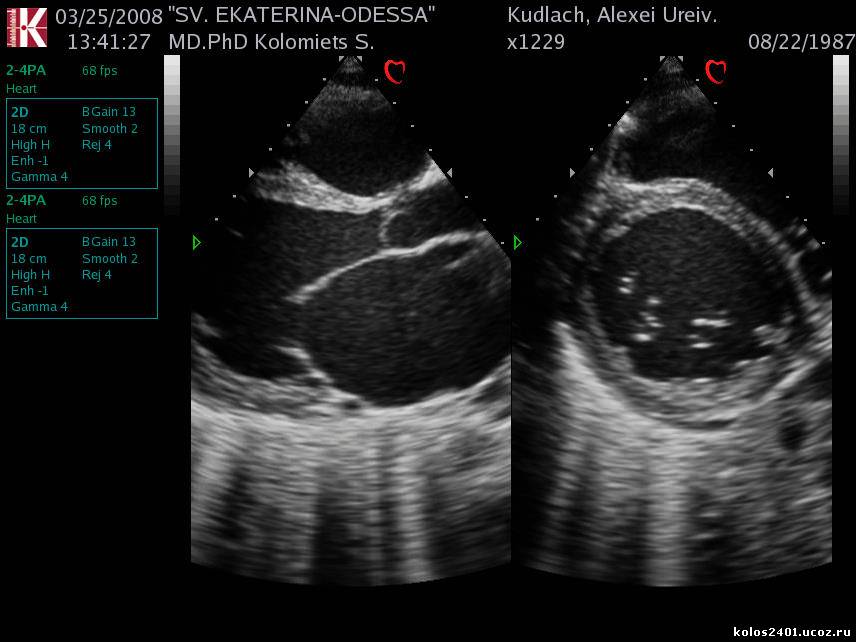

ДКМП

ДКМП-ФВ=17%

Дилатационная кардиомиопатия